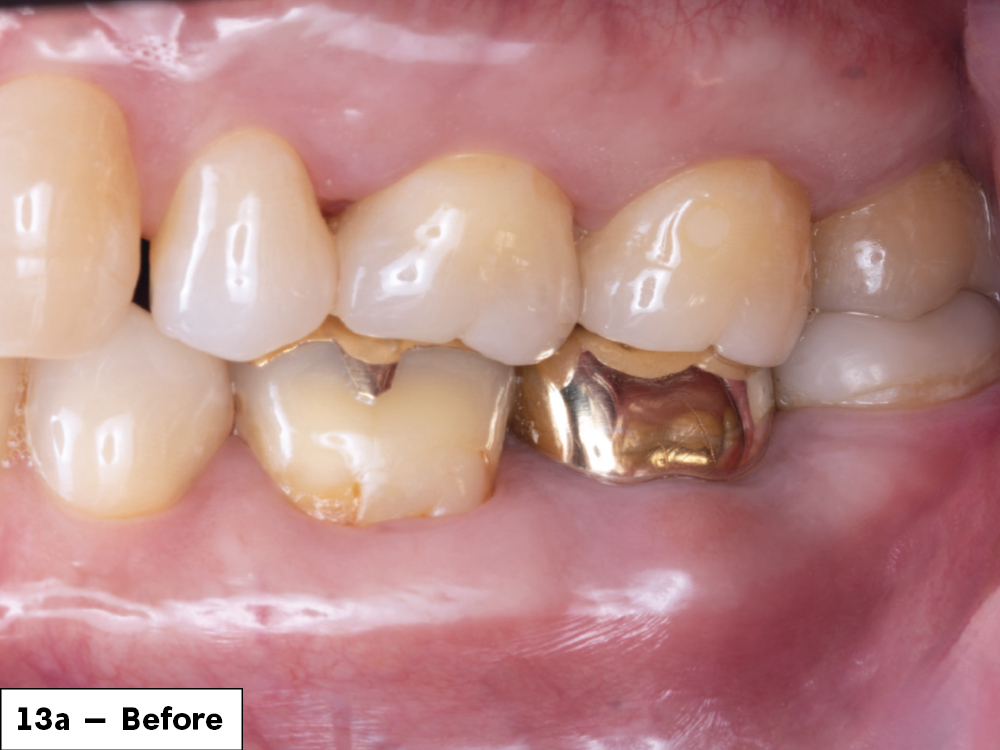

In-office milling is a quickly evolving option for the modern dental practice. With the introduction of a same-day screw-retained option, BruxZir® NOW SRC milling blocks, there’s even more opportunity for optimizing single-unit restoration workflows. In this case study, I’ll demonstrate how this product can be used as part of an efficient workflow for tooth replacement in the posterior. When combined with guided surgery and in-office crown design, this procedure offers reliable results while saving money and significantly cutting down on chair time for dentists.